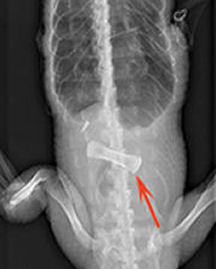

The researchers fed the alligators meals of hamburger and an oxtail bone and then X rayed the animals four times over 9 days to monitor the pace of digestion. Alligators with intact circulatory systems digested the bone more rapidly than did animals that couldn’t shunt blood, Farmer reported last week at an American Physiological Society meeting in Virginia Beach, Va.